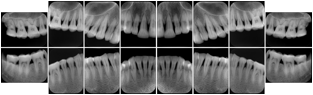

Intra-oral radiography typically involves acquisition of multiple images of various parts of the dentition. Many digital radiographic systems offer customized templates that are used for displaying the images in a study on the screen. These templates may also be referred to as mounts or view sets. The Structured Display Object represents a standard method of encoding and exchanging the layout and intended display of Structured Displays. A structured display object created in this manner could be stored with a study and exchanged with images to allow for complete reproduction of the original exam.

1. A patient visits a General Dentist where a Full Mouth Series Exam with 18 images is acquired. The dentist observes severe bone loss and refers the patient to a Periodontist. The 18 images from the Full Mouth Series along with a Structured Display are copied to a DICOM Interchange CD and sent with the patient to see the specialist. The Periodontist uses the CD to open the exam in his Dental Radiographic Software and consults via phone with the General Dentist. Both are able to observe the same exam showing the images on each user's display using the exact same layout.

Intra-oral Full Mouth Series Structured Display

Figure OO-1. Intra-oral Full Mouth Series Structured Display